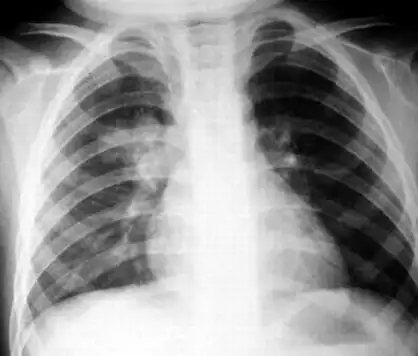

小儿支气管肺炎的介绍

【健康科普】小儿支气管肺炎与小儿支气管炎的区别

小儿支气管肺炎是怎么回事